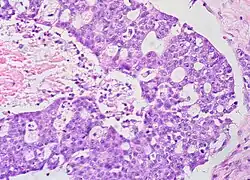

Histopathology

In case an ovarian cyst is surgically removed, a more definite diagnosis can be made by histopathology:

| Type | Subtype | Typical microscopy findings | Image |

| Functional cyst | Follicular cyst |

| |

| Ovarian cancer | Many different types, but generally severe dysplasia/atypia and invasion. |